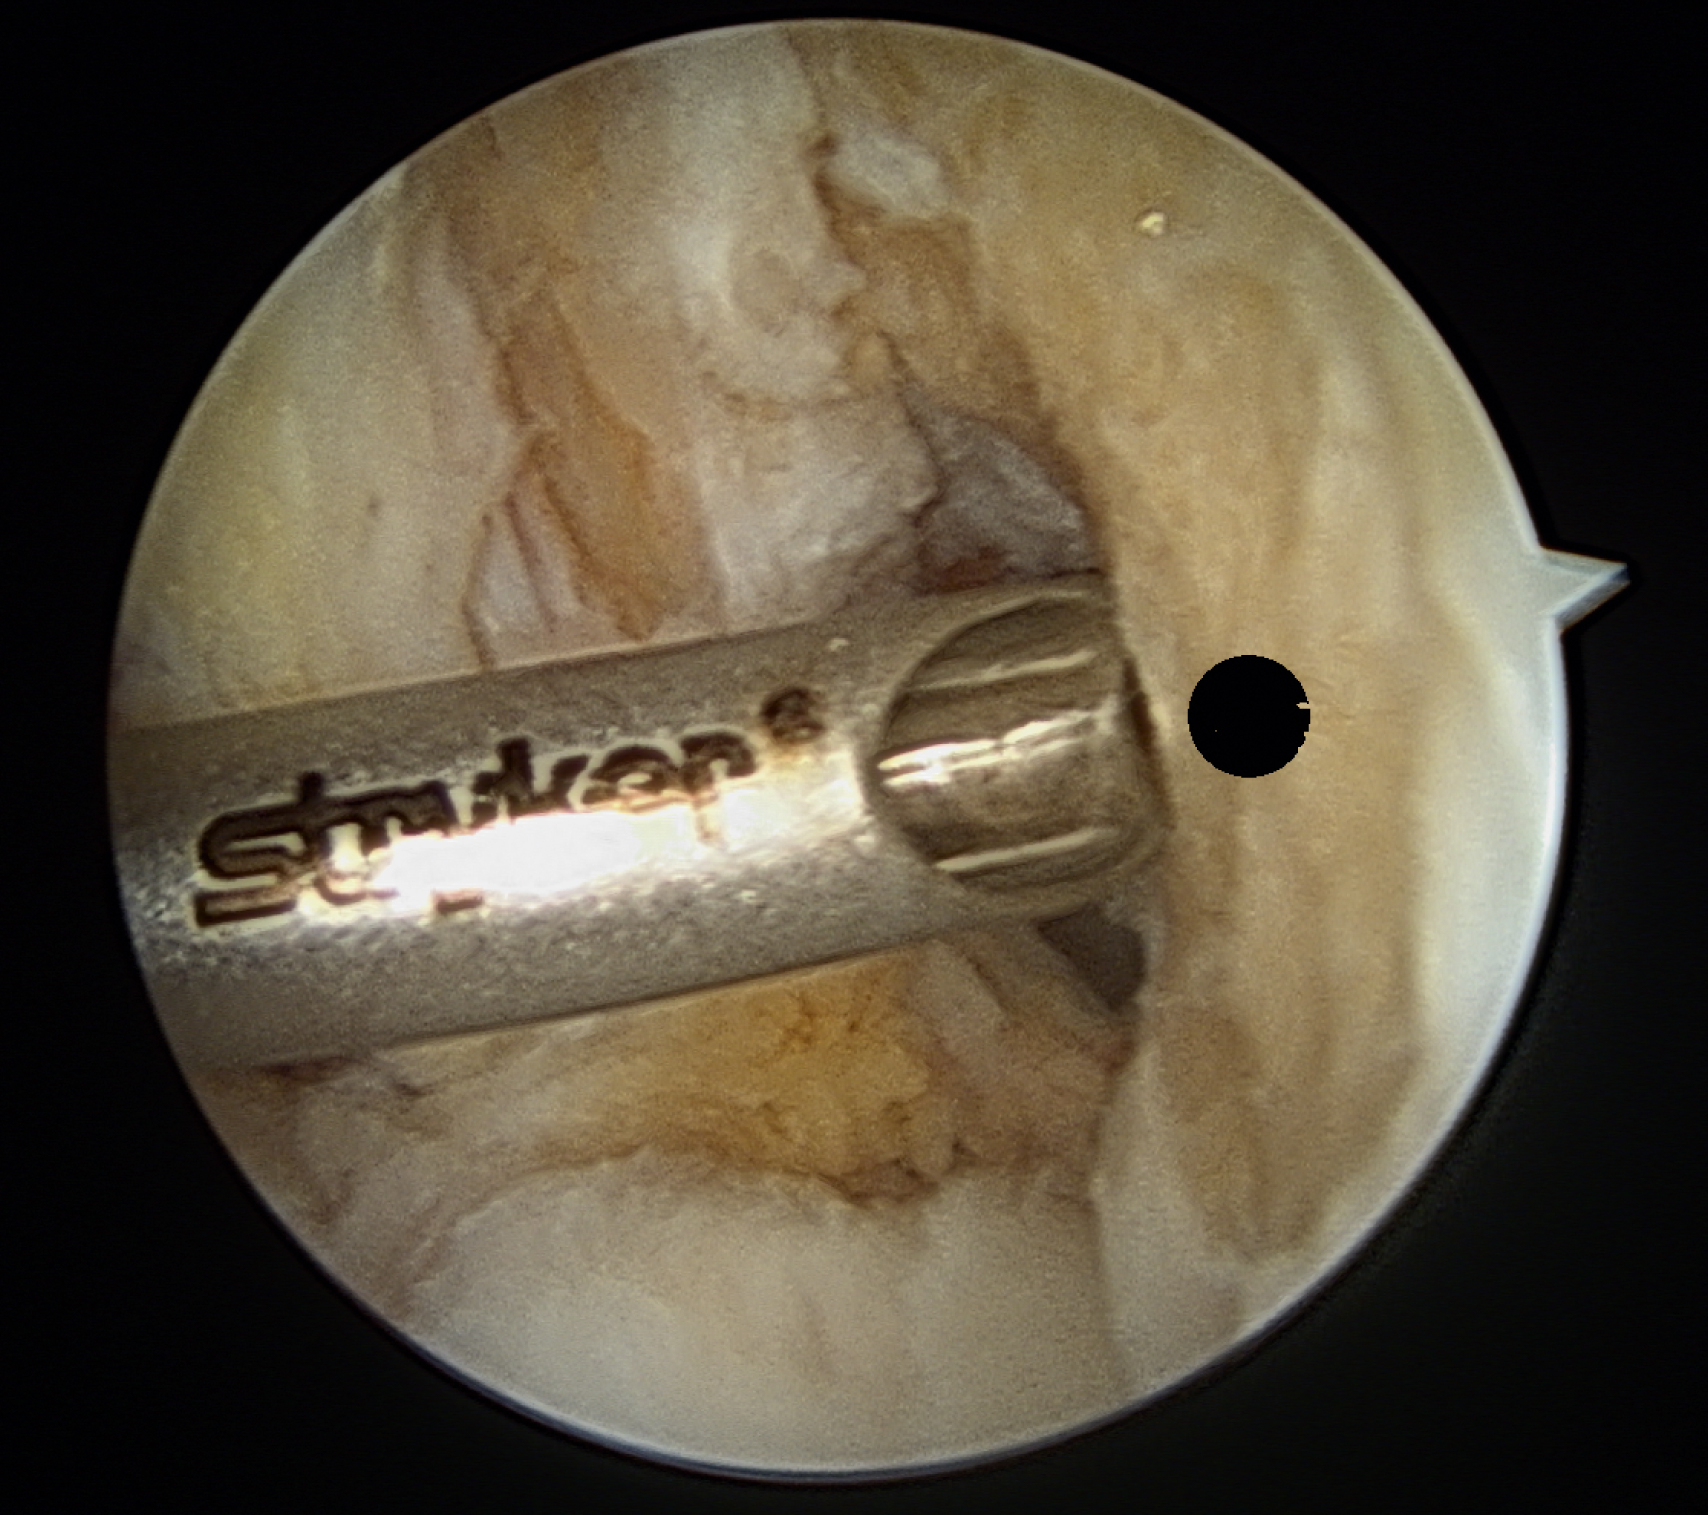

A minimal notchplasty (2 mm) of the lateral wall will facilitate visualization, and a débridement of soft tissue from the lateral wall will also help locate the ACL center. After identifying the point for the femoral tunnel, an awl is used through the medial portal to create a pilot hole for reaming (

). It is helpful to verify the position of the pilot hole by visualization through

the medial portal. The pilot hole should be approximately 8.5 mm (range 8.0–9.5 mm) up the lateral wall and slightly deep to the midpoint between the front and back of the notch (

).